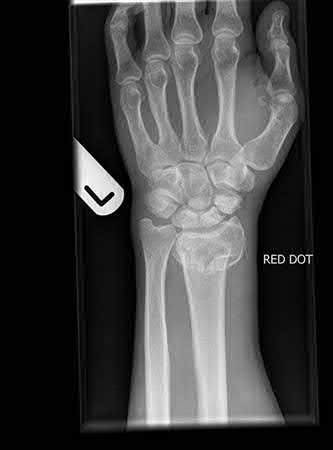

A 44-year-old male is struck by a vehicle while riding his bike. In the trauma bay, he complains of right shoulder pain . Upper extremity physical exam reveals no neurologic deficits, and an initial radiograph of the shoulder is shown in Figure A. A CT scan of the shoulder shows 1cm of posterior displacement of the tuberosity fragment. Which of the following is true regarding this injury?

The radiograph in Figure A demonstrates a posteriorly displaced greater tuberosity fracture. These injuries are often associated with anterior shoulder dislocations, and concomitant rotator cuff tears. The subscapularis attaches to the lesser tuberosity, and is not a deforming force. Open reduction and internal fixation (ORIF) is usually the treatment of choice, and it is well accepted that more than 5mm of displacement is an indication for surgery in patients that require overhead function of the arm.

Flatow et al evaluated 12 patients who were an average of five years status post ORIF of displaced greater tuberosity fractures. All fractures healed without postoperative displacement. Six patients had an excellent result and six had a good result.

Platzer et al retrospectively analyzed functional and radiographic results of 52 patients with operative treatment of displaced greater tuberosity fractures at an average time of 5.5 years from surgery compared to 9 patients with equivalent injuries treated non-operatively. Evaluation of the results of the surgical study group and the nonoperative control group, patients with reduction and fixat ion of greater tuberosity fractures had significantly better

results on shoulder function than did those with conservative treatment.